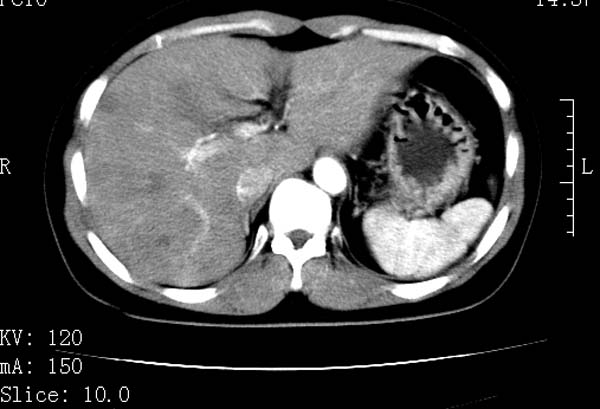

标题: CT22086:女44岁 肝右叶占位增强示巨大血管瘤,门脉期发现小 [打印本页]

标题: CT22086:女44岁 肝右叶占位增强示巨大血管瘤,门脉期发现小

支持肝右叶血管瘤诊断。 小病灶亦考虑血管瘤改变。温习一下:

肝海绵状血管瘤ct平扫常呈均匀低密度,与邻近血管密度相仿。在脂肪肝背景下可呈相对高密度。在增强扫描时,一般早期(动脉期)呈周边结节状或弧形强化,其密度与同层面的血管密度相仿,随着时间延迟向中央渐进性充填,注药后5~7分钟,逐渐扩大至全瘤强化,强化密度逐渐降至稍高于或等于正常肝脏。大的血管瘤往往中央有星形、大的低密度区,可以为纤维化或囊性变所致,纤维化成分可在延迟2 o分钟时完全充填,呈等密度,但囊变区则不会强化。不典型ct表现常见于≤3 cm的小血管瘤。小的血管瘤可以在动脉期即呈全部致密的均匀强化,不呈典型的周边结节状强化表现,但其密度往往较高,与主动脉相仿,在延迟期呈高或等密度。其他不典型的ct表现有:增强扫描强化不明显,呈点状较轻程度的强化,充填慢,可能与供血动脉较细和较大的血管间隙有关以及中央先强化等。

延迟扫描三个病灶都呈等密度改变。肝多发血管瘤,较典型。